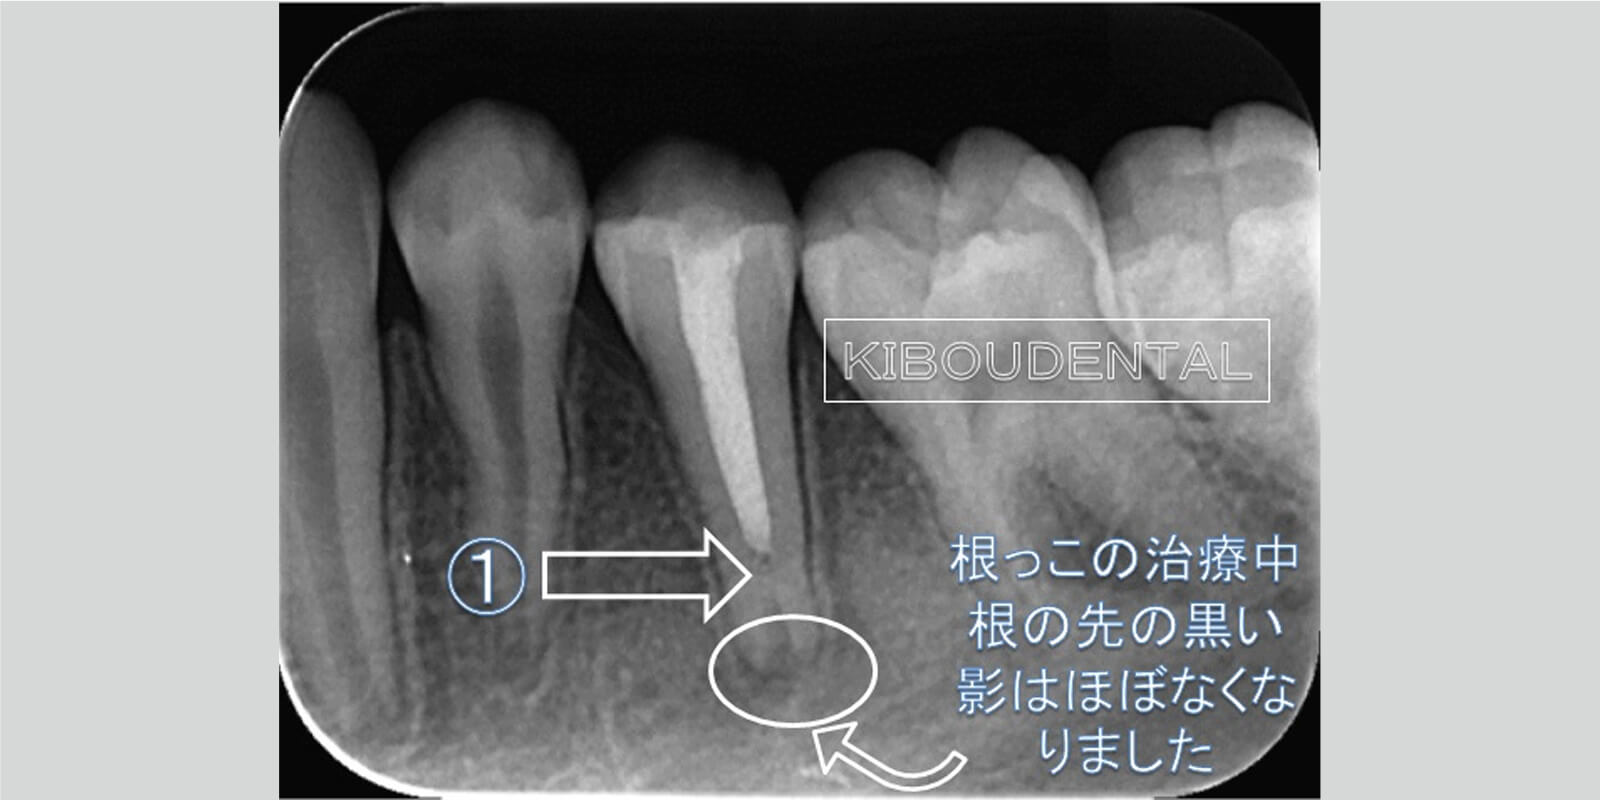

根管治療開始2か月後根管治療開始2か月後の状態です。根っこの先の黒い影は、小さくなり骨が再生してきております。また(1)の部分はデンチンブリッジが出来てきております。

治療終了最終的な神経の代わりとなるお薬を入れました。根っこの先の黒い影はほぼなくなり、骨が再生してきております。神経の治療のために削った部分も、最小限で治療を行ったのでレジン樹脂で治療を終了しました。今回の治療は、根未完成歯だったため治療期間が長くなりましたがSさん長い治療期間お疲れ様でした。